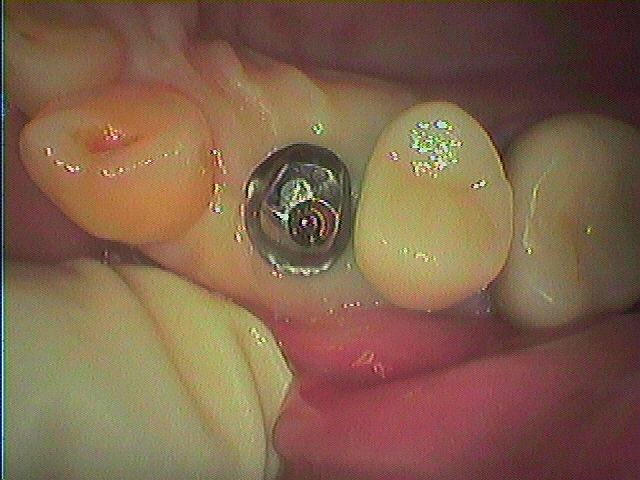

抜歯窩にも制限があり、少し傾斜しましたが良好とします。| |広島市安佐南区の歯科医院 抜歯窩にも制限があり、少し傾斜しましたが良好とします。 トップ お知らせ・ブログ 抜歯窩にも制限があり、少し傾斜しましたが良好とします。 抜歯窩にも制限があり、少し傾斜しましたが良好とします。 Web診療予約 初めての方へ 選ばれ続ける理由 院内設備について 歯が痛いしみる一般歯科 歯がぐらぐらする歯周病 健康な歯を保ちたい予防歯科 子供の虫歯予防をしたい小児歯科 銀歯をセラミックに審美歯科 白い歯を目指しませんか?ホワイトニング 矯正専門医がいるので安心矯正歯科 抜けた歯を補いたいインプラント・入れ歯 医院案内 スタッフ紹介 メリィハウス歯科クリニックオフィシャルホームページ ラベンダー歯科クリニックオフィシャルホームページ お知らせ・ブログ ホーム 診療科目 一般歯科 歯周病治療 予防治療 小児歯科 審美治療 ホワイトニング 矯正歯科 入れ歯・インプラント マウスピース矯正 初めての方へ 院長・スタッフ 設備紹介 医院案内・アクセス メニューを閉じる